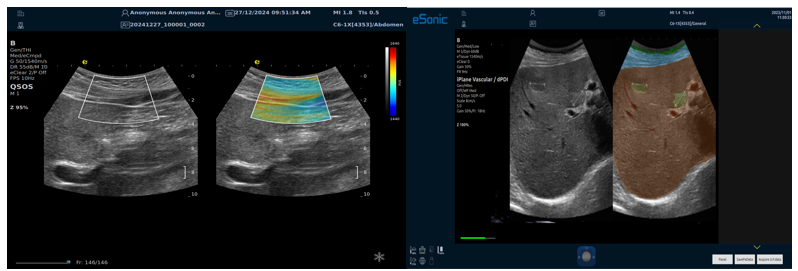

QSOS声速定量成像

QSOS声速成像技术利用声波在组织中的传播速度差异性,计算不同位置的声速值,反映组织的物理特性。

利用超声探头发射超声波脉冲,分析反射信号的时间延迟,确定声波传播路径和速度,构建声速分布图像。

图像显示

QSOS技术采用彩色编码显示声速图像,不同颜色代表不同声速值,便于医生识别病变部位和测量。

技术优势

?精准定量反映组织特性,成像更敏锐?彩色编码直观显示,轻松发现异常?捕捉声速差异,早期、微小病变更易察觉